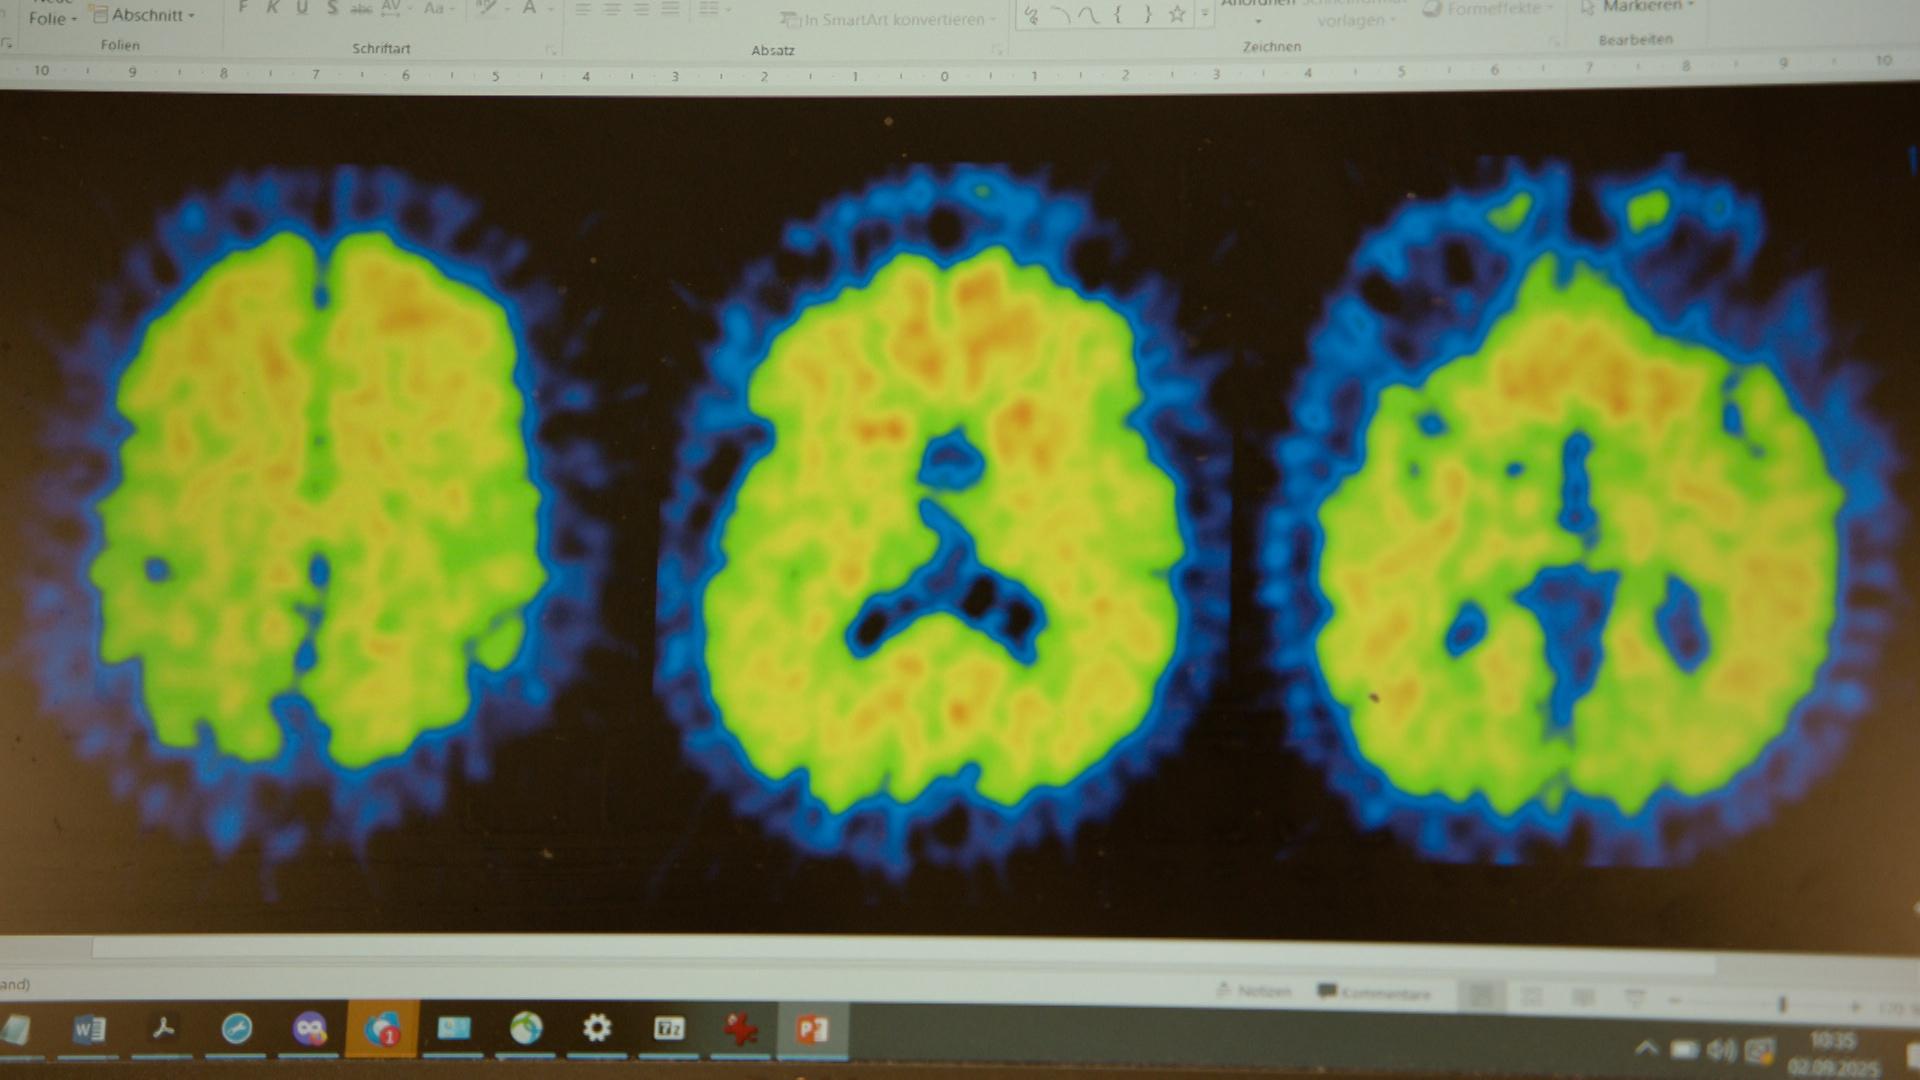

Bislang konnten bei einer Alzheimer-Erkrankung lediglich Symptome und Begleiterscheinungen behandelt werden. Das Medikament, das seit 1. September neu auf dem deutschen Markt ist, setzt bei den Ursachen der Krankheit an – es bekämpft die schädlichen Eiweißablagerungen im Gehirn, die Amyloid-Ablagerungen. Diese werden für die Entstehung von Alzheimer verantwortlich gemacht. Alzheimer ist eine Form von Demenz.

Der neue Wirkstoff Lecanemab ist ein Antikörper. Er bindet die schädlichen Eiweißablagerungen im Gehirn und aktiviert das Immunsystem, diese Ablagerungen abzubauen. Vertrieben wird der Wirkstoff unter dem Handelsnamen Leqembi. Im April 2025 hatte es die EU-Zulassung erhalten. Verabreicht wird es als intravenöse Infusion alle zwei Wochen.